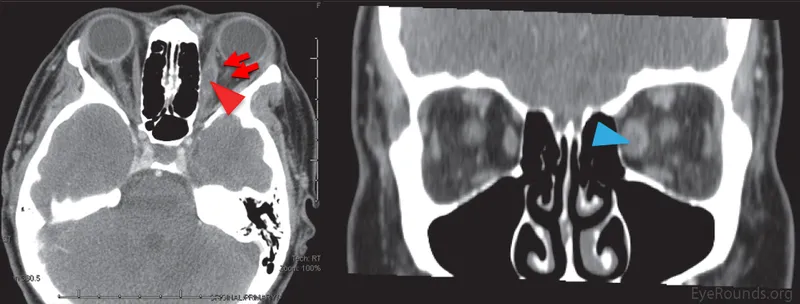

- Diagnosis: CT scan (orbit & sinuses) gold standard.

Infection posterior to orbital septum. Sight-threatening emergency.

- Orbital cellulitis: Post-septal infection, often from sinusitis; causes proptosis, painful ophthalmoplegia, ↓vision.